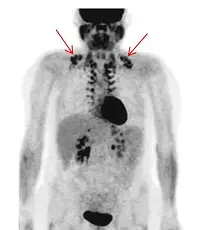

病人接受¹⁸F-FDG PET ,出現圖中紅色箭頭標註之生理性攝取現象,下列敘述何者錯誤?

這是一張 18F-FDG PET 的全身最大強度投影 (Maximum Intensity Projection, MIP) 影像。圖中紅色箭頭指向雙側頸部下端及鎖骨上區 (supraclavicular area),呈現對稱、強烈且呈多發結節狀的放射性藥物攝取。此外,在脊柱旁 (paravertebral) 區域也隱約可見類似的對稱性攝取。影像中亦可觀察到大腦、心肌、肝臟、雙側腎臟及膀胱等正常的生理性代謝與排泄。箭頭所指的特徵性對稱攝取,即為典型「棕色脂肪組織 (BAT)」活化所造成的生理性攝取,在核醫學文獻中常被稱為 "USA-Fat" (Uptake in Supraclavicular Area Fat)。

綜合上述分析,圖中箭頭所指的對稱性攝取為活化的棕色脂肪組織 (BAT)。BAT 的活化與交感神經興奮有關,使用鎮靜劑(例如 Diazepam)能有效降低交感神經張力與患者焦慮,進而抑制並減少棕色脂肪對 18F-FDG 的攝取。因此,選項 (C) 稱「使用鎮靜劑可能造成此類現象較容易發生」的敘述與臨床事實完全相反,為本題要求選出的錯誤敘述。